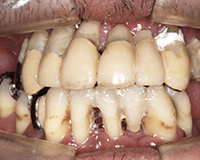

症例6#静脈内鎮静法 #歯ぎしり・食いしばりボロボロの口腔に対し、一回の手術で全てのインプラントを埋入したケースです。 -